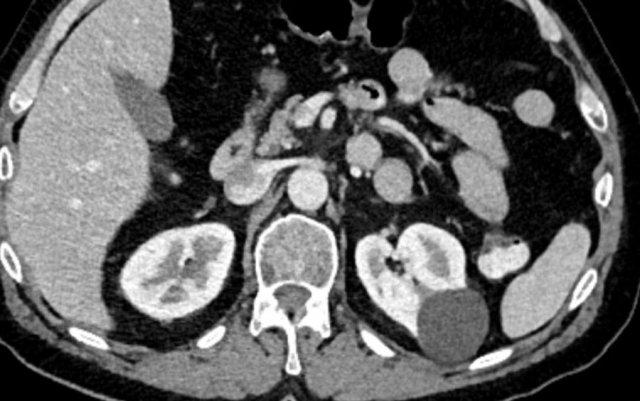

Ca lâm sàng 4

Hình chụp CT thì tĩnh mạch cửa cho thấy một tổn thương dạng nang không đồng nhất ở thận trái.

Vùng tăng tỷ trọng có ngấm thuốc trên ảnh chuỗi xung T1W có ức chế mỡ, phù hợp với một nốt đặc trong nang Bosniak 4.